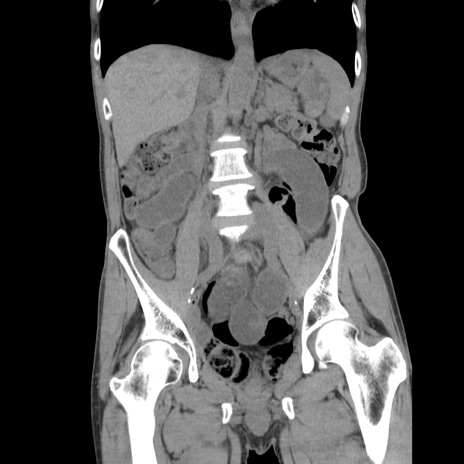

症例11(冠状断像)

【症例】 60歳代男性

【主訴】 下腹部痛

【現病歴】 本日夜中より下腹部痛の症状認め、受診。

【既往歴】 膀胱癌(膀胱全摘+尿管皮膚瘻術) 、胃癌術後

【身体所見】 BT 35.3℃、PR 58/min、BP 136/98mHg、腹部平坦、軟、腸蠕動音±、ストマ留置あり、左上腹部~正中部に圧痛あり、反跳痛なし。

【データ】WBC 5100、CRP0.01